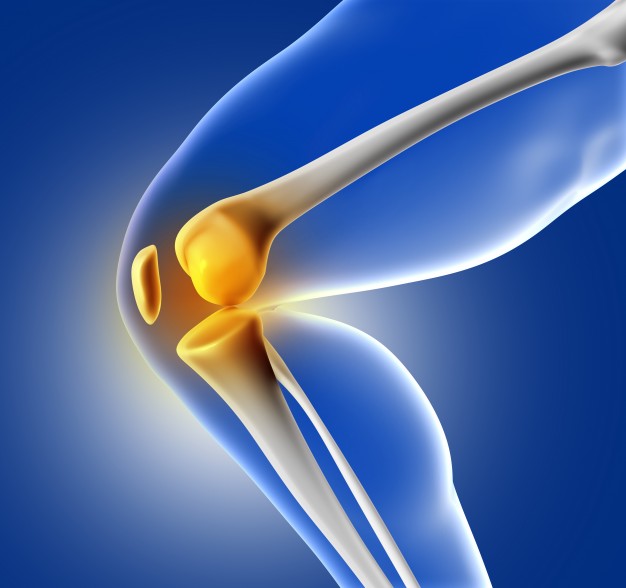

Sendi berperan penting untuk menggerakan tulang-tulang dengan mudah, jumlah sendi yang ada dalam tubuh, meliputi bahu, pinggul, siku, dan lutut.

Salah satu penyebab masalah sendi pada usia muda yang umum adalah radang sendi atau artritis. Untuk itu, bagaimana cara mengatasinya?